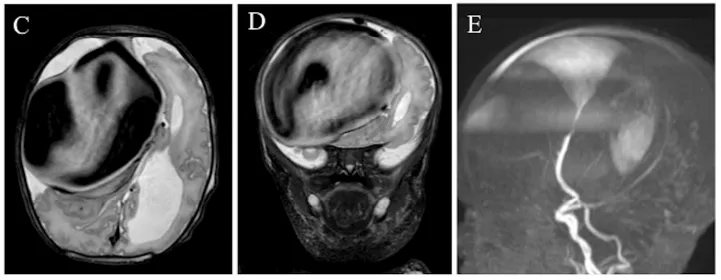

出生第1天,亨利被确认存在颅内血管病变,表现为囊状动脉瘤样结构,内部为搏动性血流。同日进行的磁共振血管成像(MRA)显示右侧额叶软脑膜动静脉瘘(PAVF),伴软脑膜静脉瘤样扩张,其内血流湍急,经扩张静脉引流入上矢状窦(图1C-E)。该病变还压迫同侧脑组织,导致局部脑实质萎缩。

因亨利临床状态稳定,医疗团队决定在其出生后第8天施行数字减影血管造影(DSA),以完成血管内栓塞治疗。术后即刻造影显示主瘘道实现完全闭塞(图2C)。

术后5小时经前囟彩色多普勒检查确认软脑膜静脉瘤样扩张段已无残余血流,上矢状窦回流通畅。